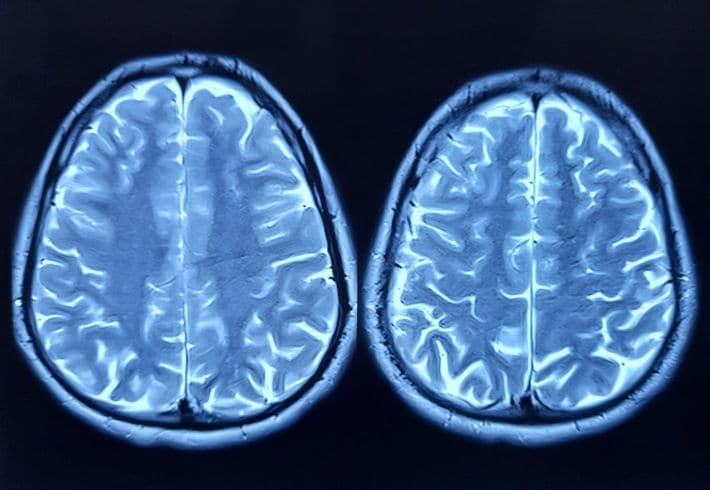

「玉ねぎが重くて持てない」から始まった…肝っ玉母さんが42歳で脳梗塞、半身不随で20歳娘の"30年介護"の粛々

※写真はイメージです